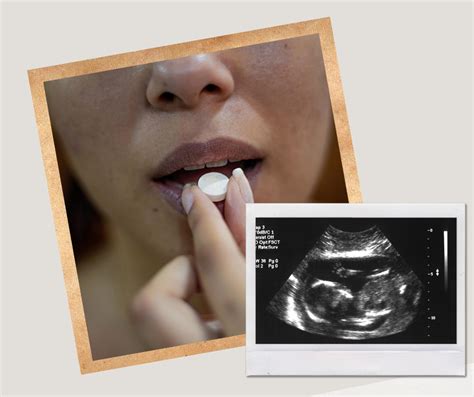

Medikamentinis nėštumo nutraukimas, dar vadinamas vaistiniu abortu, yra procedūra, kurios metu naudojami receptiniai vaistai, siekiant nutraukti nėštumą jo ankstyvosiose stadijose. Šis metodas, laikomas mažiau traumuojančiu ir saugesniu nei chirurginis, nereikalauja narkozės ir medicininės intervencijos, todėl komplikacijų rizika yra mažesnė.

Procesas paprastai apima dviejų vaistų - mifepristono ir misoprostolio - vartojimą. Pirmasis vaistas, mifepristonas, stabdo hormono progesterono gamybą, taip sustabdydamas embriono vystymąsi. Antrasis vaistas, misoprostolis, sukelia gimdos susitraukimus, kurie galiausiai lemia nėštumo nutraukimą. Moteris, gavusi gydytojo receptą, vaistus gali suvartoti jai patogiu laiku ir patogioje aplinkoje.

Nėštumą medikamentiniu būdu galima nutraukti iki devintos nėštumo savaitės (8 savaitės ir 6 dienos). Šiam metodui nereikia bendrosios nejautros, o procedūra gali būti atliekama ambulatoriškai, suteikiant didesnį privatumą. Dažniausiai pasireiškiantys šalutiniai reiškiniai yra pykinimas, silpnumas, karščiavimas, tačiau itin reti atvejai, kaip septinis šokas, gali kelti grėsmę gyvybei. Po procedūros rekomenduojama savaitę ar dvi vengti lytinių santykių ir kreiptis į gydytoją pakartotinei konsultacijai po 7-14 dienų, kad būtų įvertinta sveikatos būklė ir patvirtintas sėkmingas nėštumo nutraukimas.